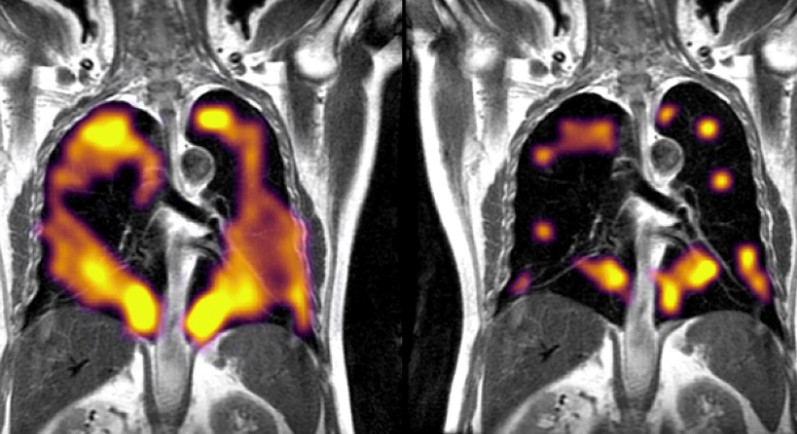

옥스퍼드 대학과 셰필드 대학의 연구팀은 코로나 19 폐렴으로 퇴원한 환자 9명과 건강한 일반 대조군 5명을 대상으로 특수 폐 MRI 검사법인 과분극 제논 MRI (hyperpolarised xenon MRI (XeMRI), 129XeMRI)

검사를 진행했습니다.

129XeMRI는 제논을 조영제로 사용해서 폐의 구조는 물론 폐포의 가스 교환 능력까지 알 수 있습니다.

그 결과

예상했던 대로 코로나 19 폐렴으로 입원치료를 받았다가 퇴원한 모든 환자에서 폐 손상을 확인할 수 있었습니다.

In a paper published in Radiology, the world's leading radiology journal, the researchers from the University of Oxford and University of Sheffield said that hyperpolarised xenon MRI (XeMRI) scans had found abnormalities in the lungs of some COVID-19 patients more than three months—and in some cases, nine months—after leaving hospital, when other clinical measurements were normal.

Professor Jim Wild Head of Imaging and NIHR Research Professor of Magnetic Resonance at the University of Sheffield, said: "The findings of the study are very interesting. The 129Xe MRI is pinpointing the parts of the lung where the physiology of oxygen uptake is impaired due to long standing effects of COVID-19 on the lungs, even though they often look normal on CT scans.

The study's principal investigator at Oxford Professor Fergus Gleeson, Professor of Radiology at the University of Oxford and Consultant Radiologist at Oxford University Hospitals (OUH) NHS Foundation Trust, said: "Many COVID-19 patients are still experiencing breathlessness several months after being discharged from hospital, despite their CT scans indicating that their lungs are functioning normally.

"Our follow-up scans using hyperpolarized xenon MRI have found that abnormalities not normally visible on regular scans are indeed present, and these abnormalities are preventing oxygen getting into the bloodstream as it should in all parts of the lungs."